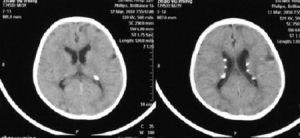

2.頭顱CT或MRI

平掃可見室管膜下腦室邊緣及大腦皮層表面多個結節狀稍低或等密度病灶,部分結節可顯示高密度鈣化,為雙側多發性,增強呈普遍增強,結節更清晰,可發現平掃不能顯示的結節。皮層和小腦的結節有確診意義。